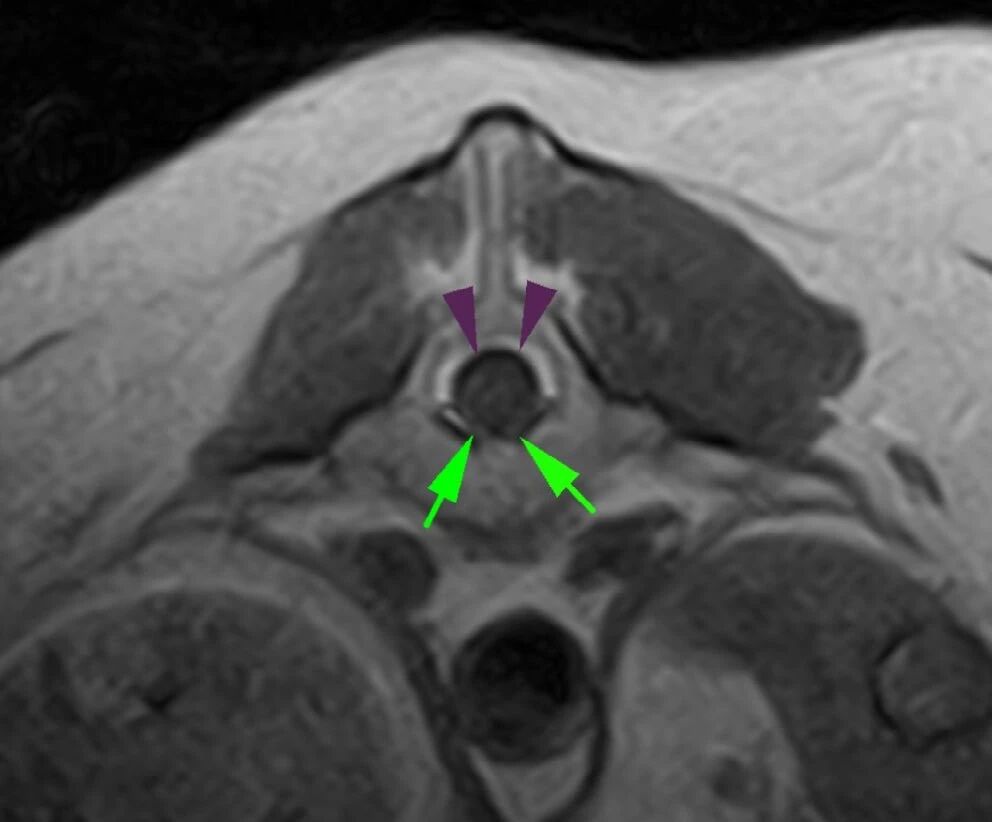

可见左后肢及臀部肌肉明显萎缩,腰骶部椎管内及增大的左侧L7神经根处出现轻度造影剂强化(下图)。据此推测左侧L7/S1椎间隙存在脊神经炎症,导致神经源性肌肉萎缩。

↑ L7-S1脊柱的CT图像(横截面,软组织重建,经过对比后),显示了增大的神经(箭头)和周围组织的轻度对比增强(三角)。